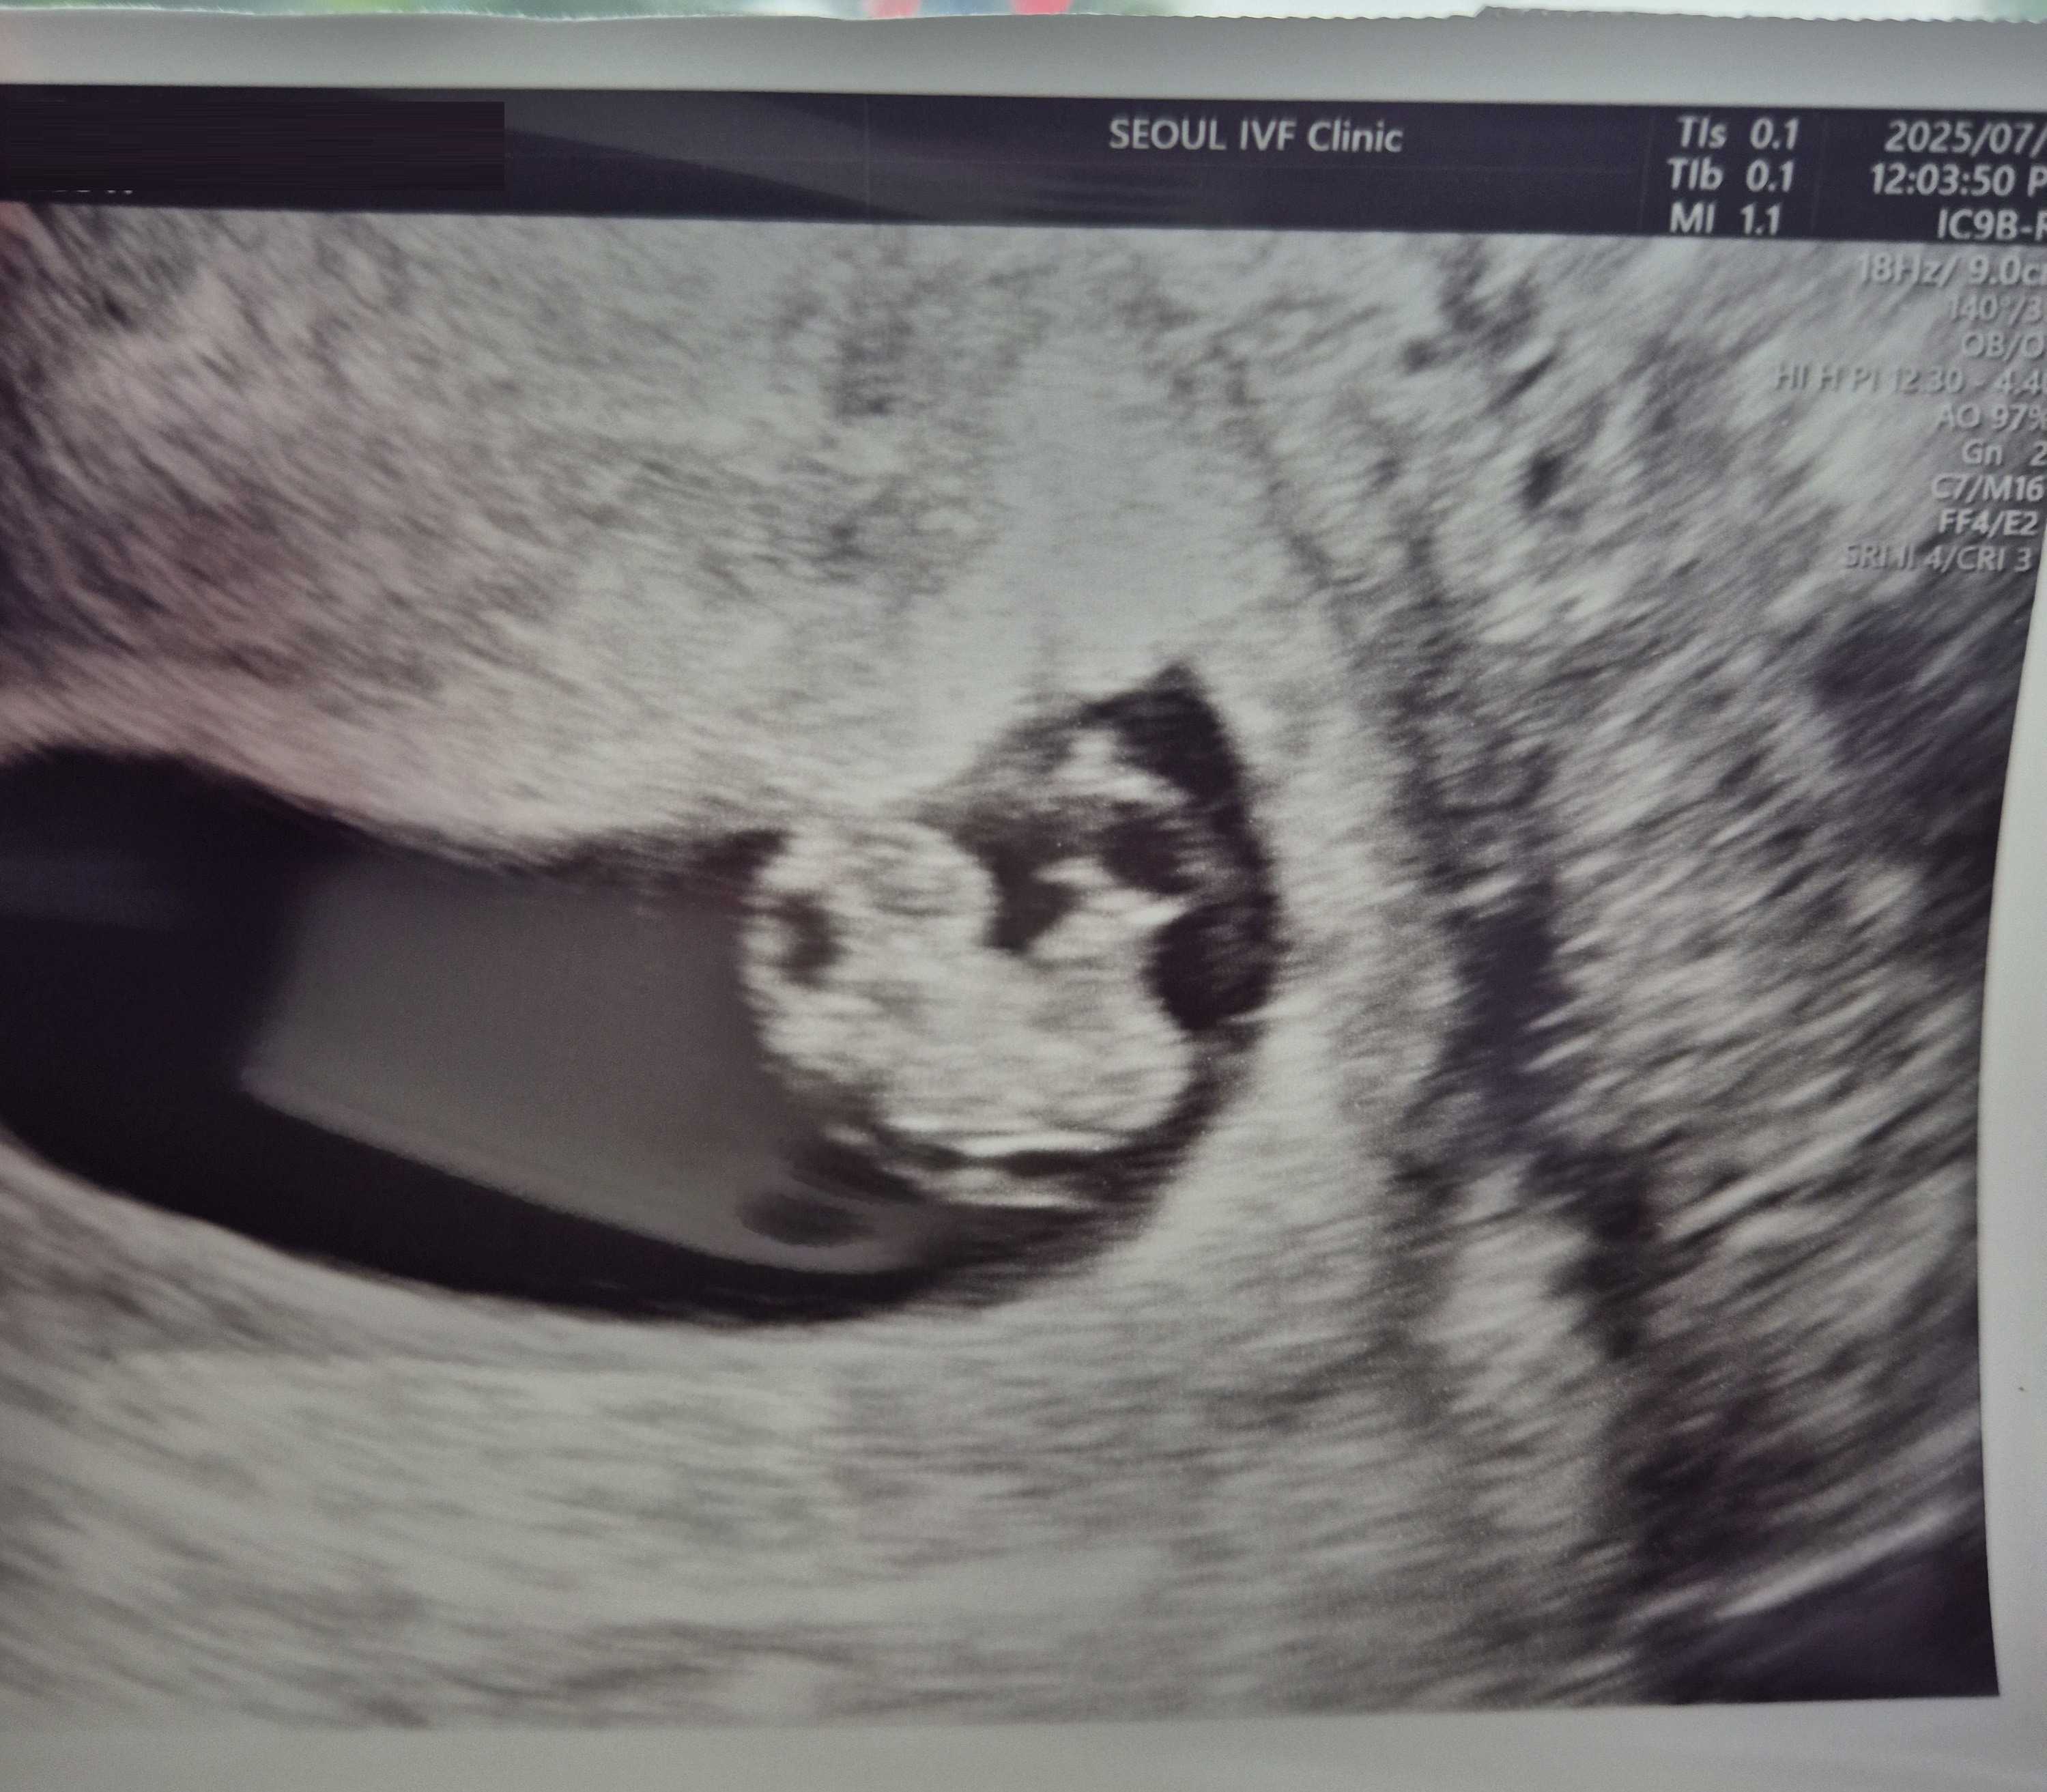

| 가슴 떨리는 임신 이야기를 공유해 주세요. | 매달 기대와 실망을 반복하기도 했지만, 결국은 “우리에게 꼭 올 아가”라는 믿음을 가지고 긍정적인 마음으로 기다렸습니다. 그래서인지 설렘이 더 컸던 것 같아요^^. 마침내 시험관 1차 시도만에 임신에 성공했을 때는 너무 기쁘고 벅차서 지금도 그 감동이 잊히지 않습니다. 곧 졸업을 앞두고 있어 더욱 떨리고, 이 아이를 꼭 끝까지 잘 지켜내겠다는 다짐을 하게 됩니다. |